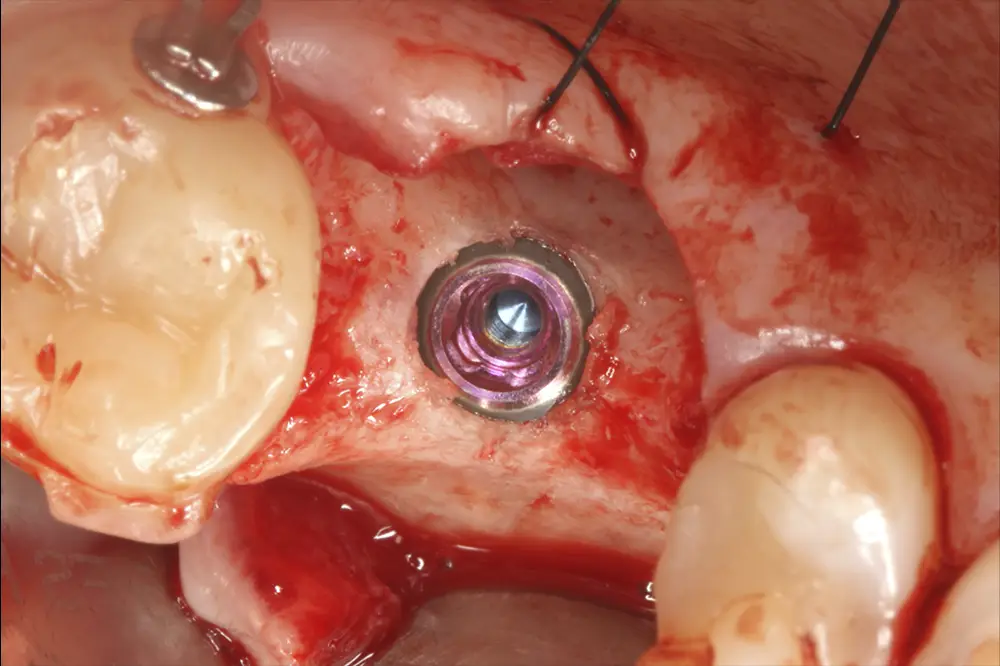

Se realizó la inserción implantaria mediante un abordaje transalveolar de elevación crestal descrito por nuestro grupo de estudio29,30. El procedimiento comenzó con el fresado del lecho receptor a bajas revoluciones, siguiendo un protocolo de fresado biológico orientado a preservar la vitalidad ósea. Se mantuvieron aproximadamente 1,5 mm de hueso residual en contacto con la membrana de Schneider para evitar su perforación durante las fases iniciales. El milímetro final fue abordado con una fresa de corte frontal diseñada específicamente para trabajar en proximidad a estructuras anatómicas sensibles, minimizando el riesgo de lesión de la membrana sinusal. A través del acceso crestal, se aplicó una presión controlada y progresiva (con la posibilidad de interponer una membrana de fibrina como elemento amortiguador) para inducir un despegamiento delicado de la membrana de Schneider. Este paso permitió completar el fresado de la cortical remanente con mayor seguridad y sin comprometer la integridad de la membrana. Una vez conseguida la elevación controlada, se procedió a la colocación del material de injerto. En este caso se utilizó hueso autólogo particulado y PRGF-Endoret. Tras la correcta adaptación del injerto, se insertó el implante alcanzando la estabilidad primaria planificada. Cinco meses tras la cirugía de elevación crestal con inserción del implante de 4,5 mm, podemos observar un TAC de control donde se aprecia el volumen óseo incrementado, llegando hasta 9,1 mm (fig. 5).

Fig. 5. Injerto óseo una vez consolidado tras la cirugía inicial. Ahora disponemos de 9 mm de volumen óseo y el implante puede ser recambiado por otro de mayor longitud para que la rehabilitación unitaria sea más favorable.